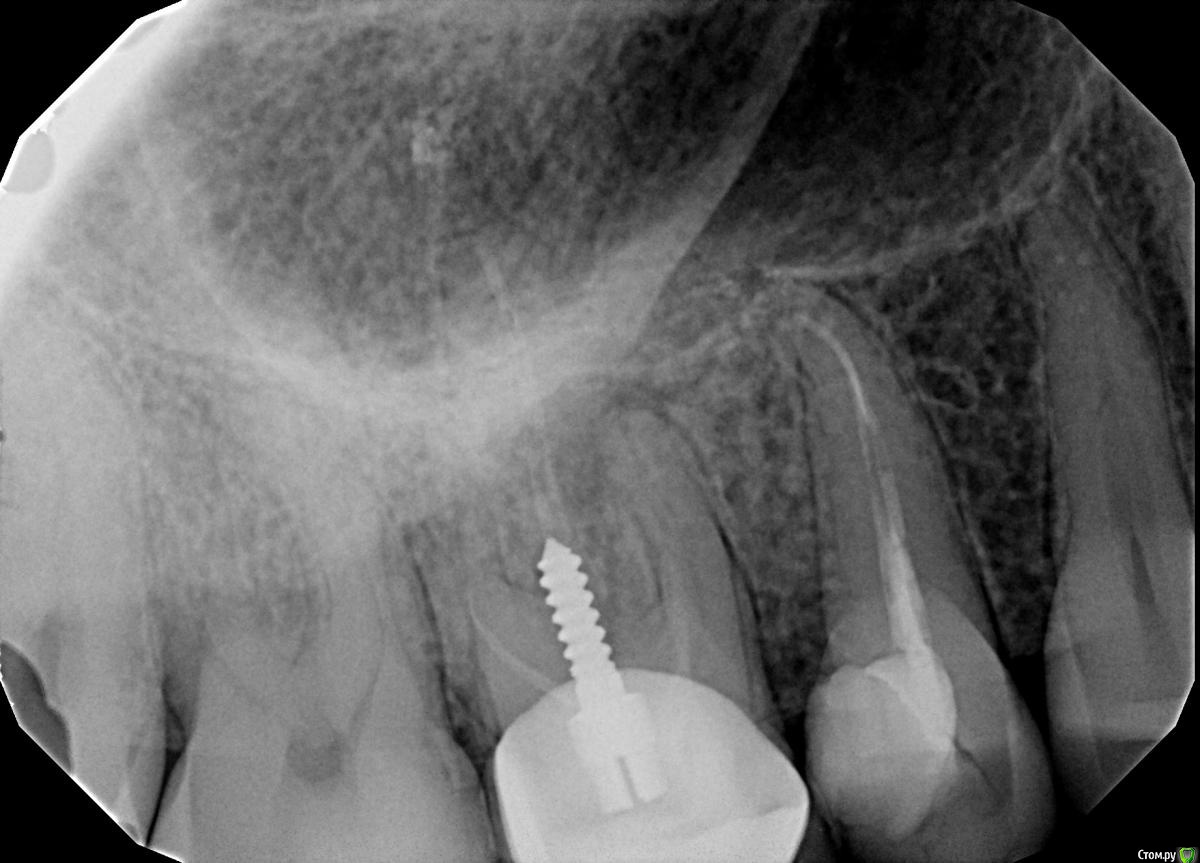

Сломался 15 верхний справа.

post-6232-0-53251200-1478030957_thumb.jpg

зуб думаю в принципе спасабельный только придется с десной повозиться и затем запротезировать, в 1.6 надо каналы перелечить

Удаление с одномоментной имплантацией. Остальное от лукавого.

Внесу свои пять копеек. Зуб спасти можно, но без всяких резаний десны нёбно, уж лучше имплантация. Зуб спасается следующим образом - в два соседних устанавливается нитиноловая дуга, и производится экструзия премоляра. При ОДНОМ условии - отсутствие других трещин. Естественно, специалист должен быть профессионалом своего дела, чтобы выполнить такую работу. Если такого специалиста нет - то лучше имплантация.

По зубу номер шесть - перелечивание и протезирование. Если Вас эта история может чему-то научить, так только тому, что надо предотвратить перелом других зубов, которые пролечены схожим образом. Всего хорошего, ищите доктора !